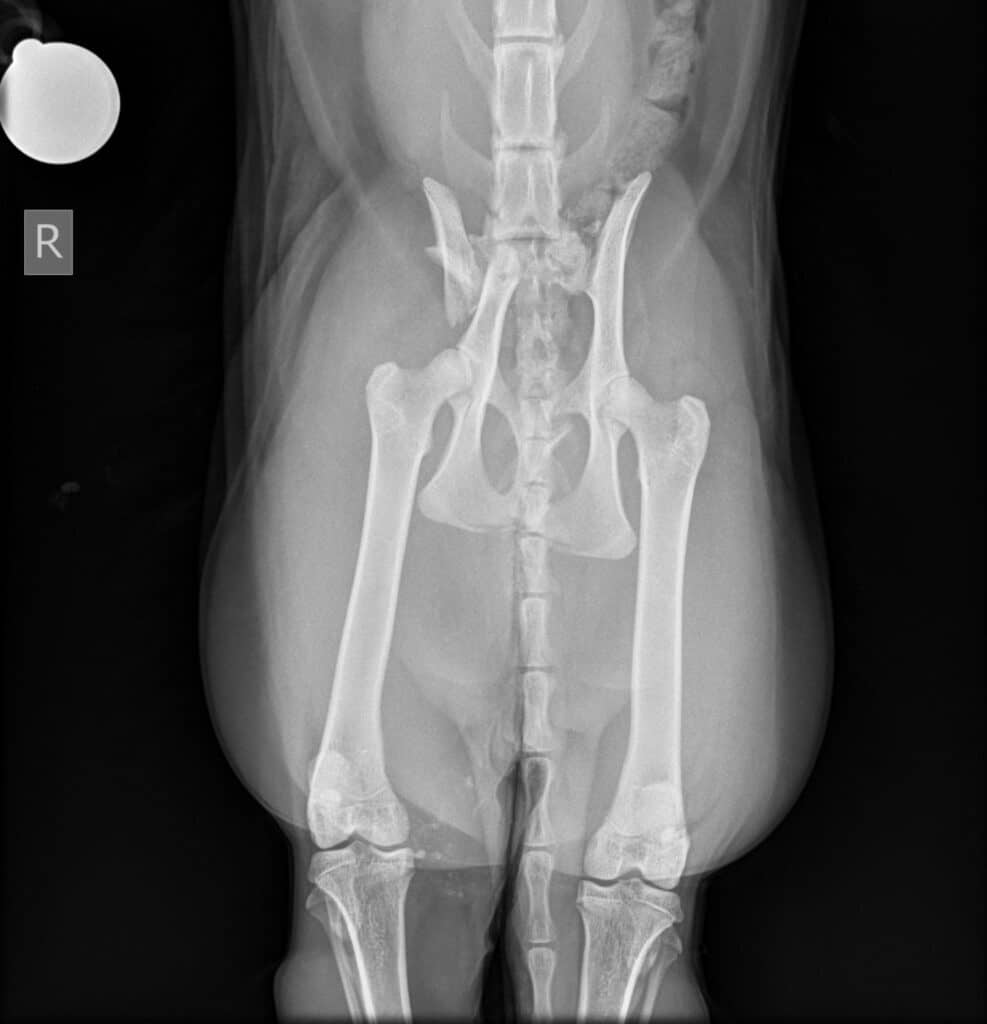

Matthew Eayrs, one of our Consultants in Orthopaedic surgery said: “When Buddy arrived with us, he was in a very serious condition and was not able to walk with a severe right pelvic lameness. A radiograph confirmed severe pelvic fractures which meant Buddy needed an urgent operation to give him the best chance of walking again. The surgery itself involved repairing the fractures with pins. A post-operative radiology revealed good fracture fragment alignment and implant positioning.”